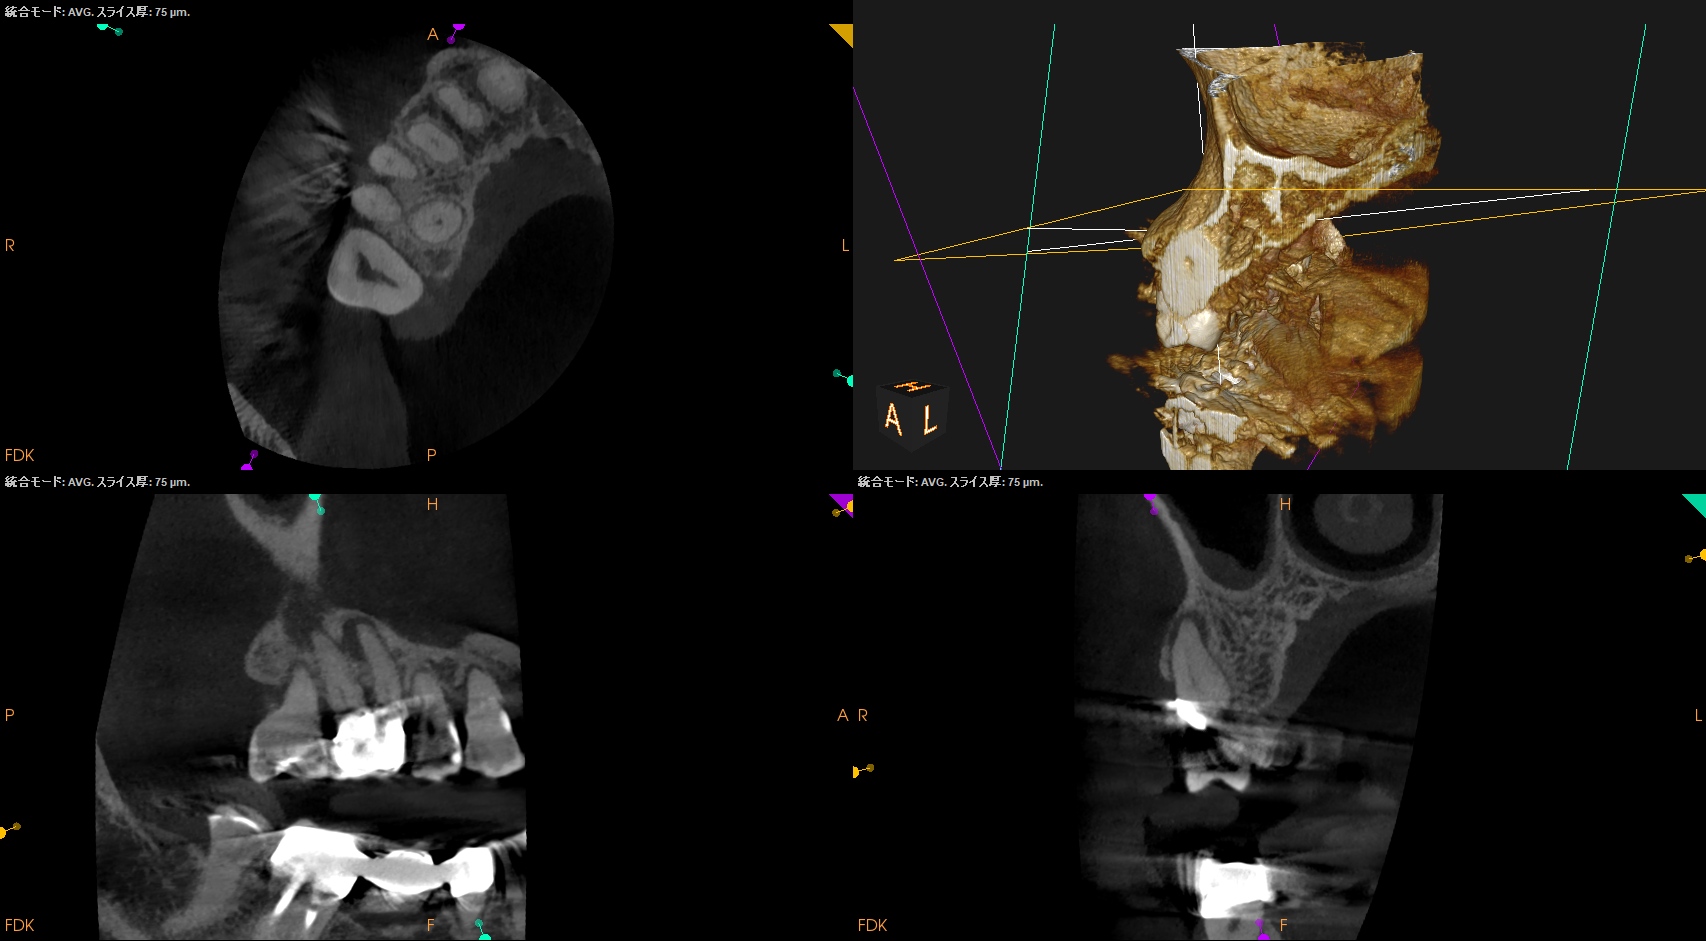

#3 RCT(2025.1.27)

PがUnderextensionの根充のような印象を与える…

が、時間が経過しないと治癒するか否かはわからない。